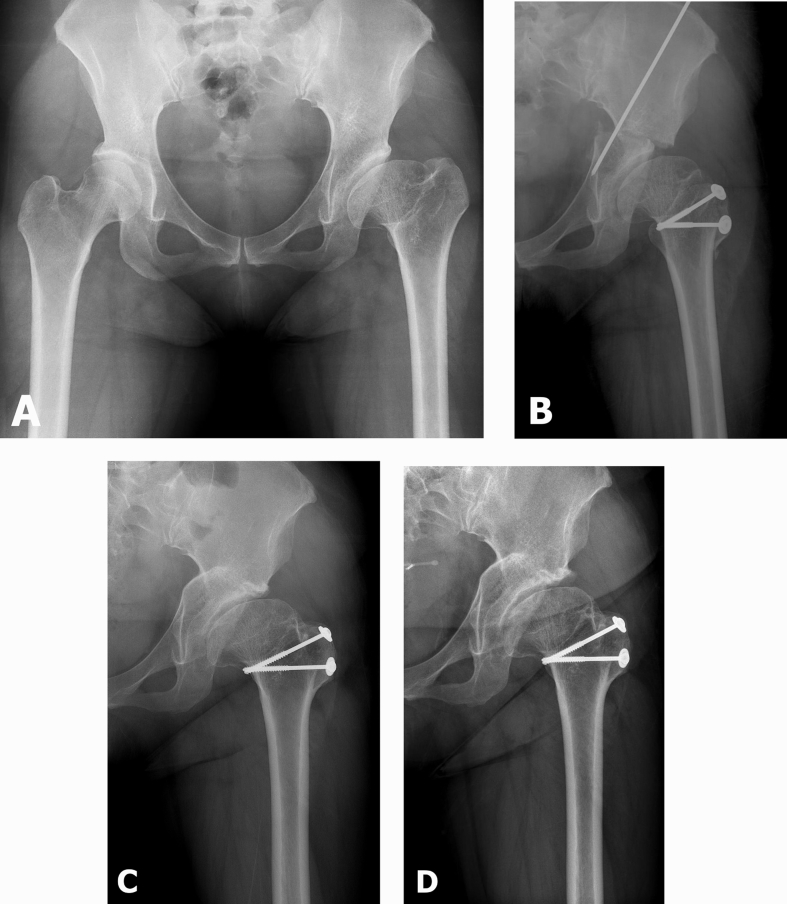

Fig. 2.

(A) Preoperative radiograph of a 30-year-old female with left hip sequelae of Perthes' disease (Stulberg IV); (B) Immediate postoperative radiograph; (C) Radiograph at 6-year follow-up; (D) Joint space was maintained at 12-year follow-up. At this time, the patient was asymptomatic.